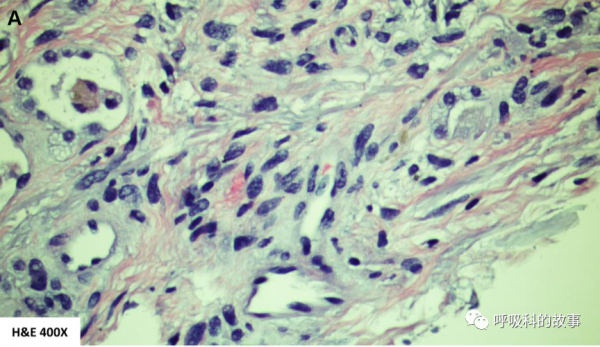

主管醫生再次行支氣管鏡檢查和肺泡灌洗,肺泡灌洗液中沒有嗜酸細胞,這表明嗜酸細胞肺炎或與BAL高嗜酸細胞相關的間質性肺病(結締組織病、藥物性肺炎、肉瘤病或肺朗格漢斯細胞組織細胞病)基本可以排除了。此外,BALF針對感染性疾病和肺癌的檢查也是陰性的。開胸右肺活檢顯示機化性急性肺損傷,伴有機化性纖維素性胸膜炎和斑片狀的肺實質梗塞,伴有大量血管內機化性血栓,沒有惡性腫瘤的證據(圖5)。

這一次氣管鏡進一步行支氣管內超聲掃描,發現隆突下淋巴結腫大,於是進行超聲下淋巴結穿刺活檢,病理顯示大片壞死,沒有肉芽腫性、感染性和惡性細胞的證據。最後,對左下葉的結節進行了穿刺活檢,發現惡性的梭形細胞腫瘤。